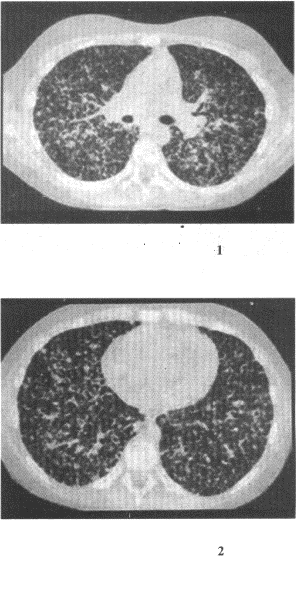

患者女,19歲,低熱,盜汗,乏力,咳嗽1個(gè)月余。

15.CT檢查如圖,最可能的診斷是

正確答案:15.C;16.A;17.D 解題思路:CT上兩肺呈彌漫性粟粒性結(jié)節(jié)狀密度增高影,有典型的三均勻征象,即分布、大小、密度均勻,并有結(jié)核中毒癥狀,可診斷為粟粒型肺結(jié)核。